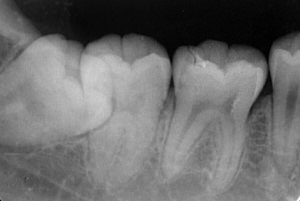

CTやデンタルX線などを使い、歯の状態を詳しく診断し、

歯の破折や根尖病変の状態、治療の適応性を確認します。

約4〜6ヶ月の経過観察を行い、X線や臨床所見で再生の進

痛み・腫れ・根尖の硬化像・根の成長(若年者)などをチェックします。